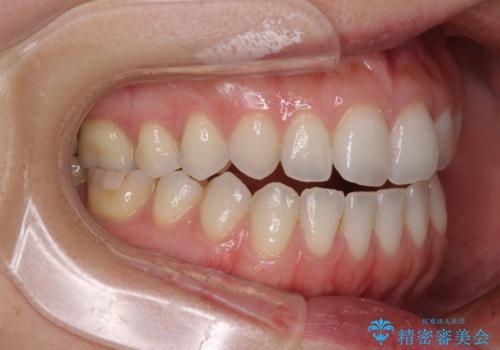

【モニター】狭い上顎歯列とオープンバイト 急速拡大装置を用いた矯正治療

- 前歯の開咬を気にして来院された患者様です。

上顎歯列が狭窄していたため、急速拡大装置により上顎骨を側方に拡大し、その後インビザラインにて矯正治療を行うこととしました。

舌の突出癖が開咬の原因であったので、改善のための舌トレーニングを行っていただきました。

舌トレーニングは後戻りにも大きく影響するため、とても重要なトレーニングです。